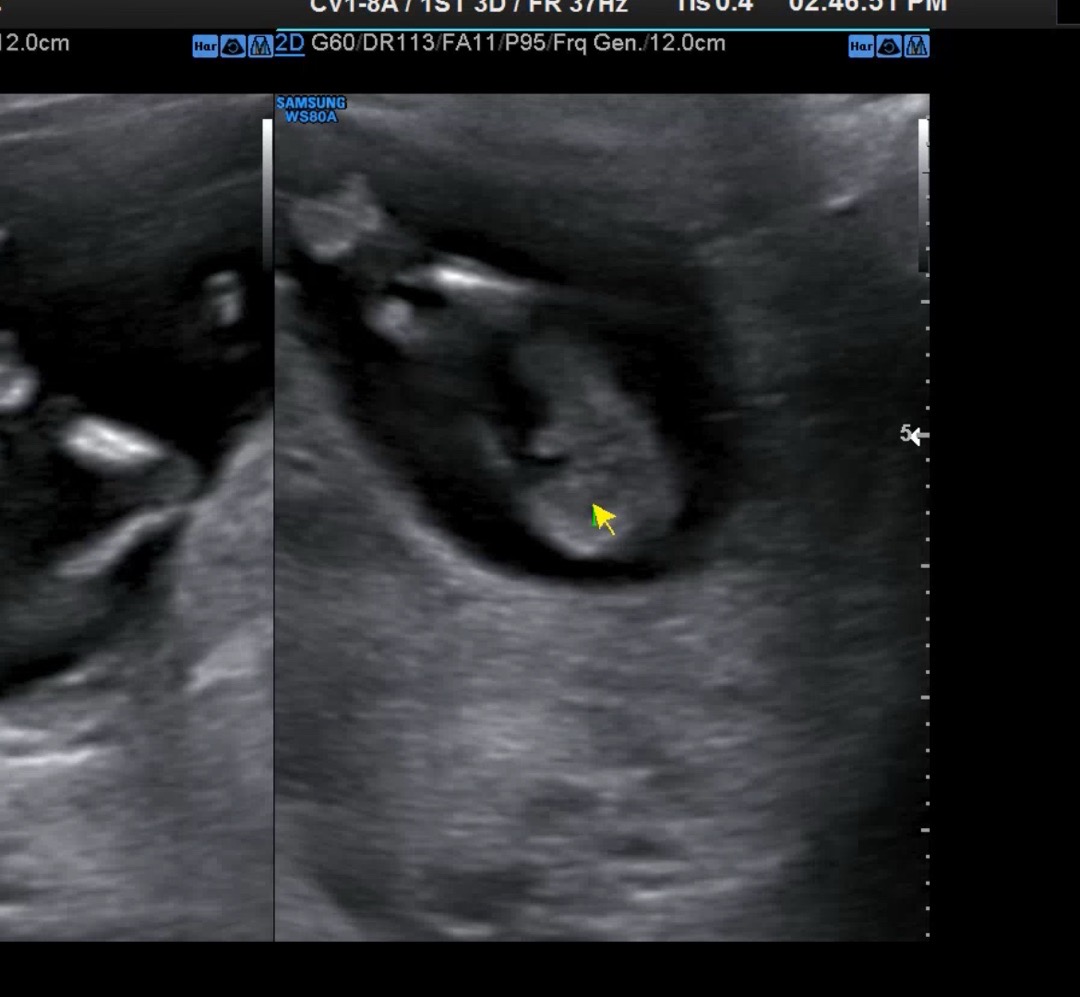

다리사이에 보이는게 뭘까요..?

다리사이에 저런게 보이는데 뭘까요? 성기치고는 가랑이 사이가 아니라 허벅지에 붙어 있어서요! 탯줄일까요?